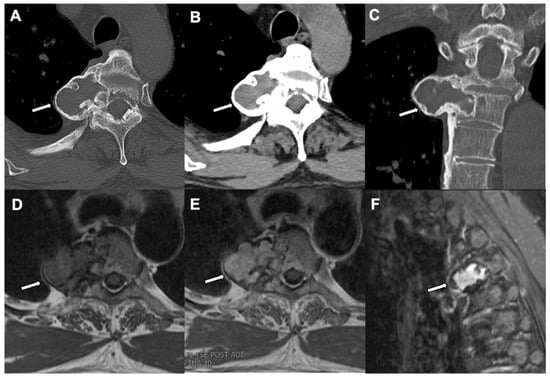

5. Osteoid Osteoma

| Radiographic/CT features | Juxtacortical, well-circumscribed homogenous sclerotic lesion | Homogenous intra-medullary sclerotic focus with spiculated margins | Small (less than 2 cm) cortical lucency with extensive surrounding sclerosis | Expansile large (more than 2 cm) lucent lesion with matrix mineralization |